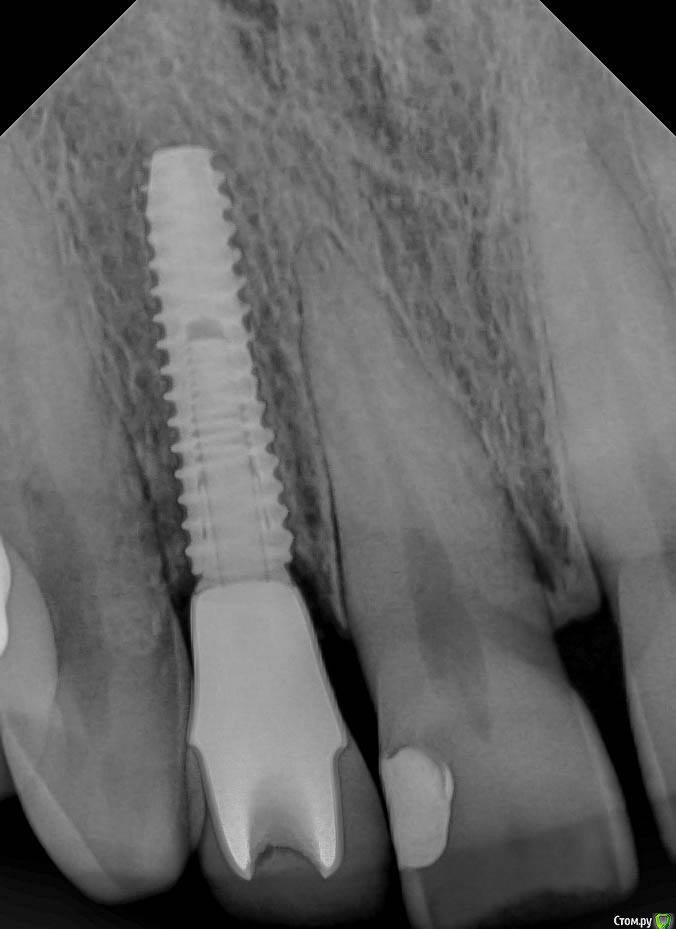

Smileee Опубликовано 15 ноября, 2018 Поделиться Опубликовано 15 ноября, 2018 (изменено) На втором снимке трещина абатмента? Изменено 15 ноября, 2018 пользователем Smileee Ссылка на комментарий

kamranchick Опубликовано 15 ноября, 2018 Автор Поделиться Опубликовано 15 ноября, 2018 На втором снимке трещина абатмента? как сказал ортопед, отклеился циркон от Ti-Base и он треснул Ссылка на комментарий

Smileee Опубликовано 15 ноября, 2018 Поделиться Опубликовано 15 ноября, 2018 как сказал ортопед, отклеился циркон от Ti-Base и он треснулКМК если б циркон отклеился, он бы вместе с коронкой выпал бы. Скорее всего просто абатмент треснул, без отклейки. 2 Ссылка на комментарий